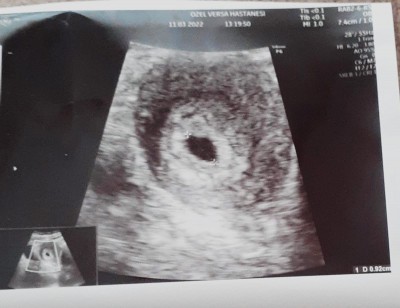

Kizlar bugun bebisimin  kese görümüne gittim cook mutluyum sizinle paylasmak istedim :)    cok guzel bir hiss cok guzel bir duyguu  gercekten ANNE OLANLARIN VE ANNELERIMIZIN HAKKI ASLAA ODENMEZ :)